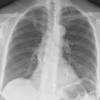

Normal PA

24 yo male

Date: 06/08/2016

Views: 6522